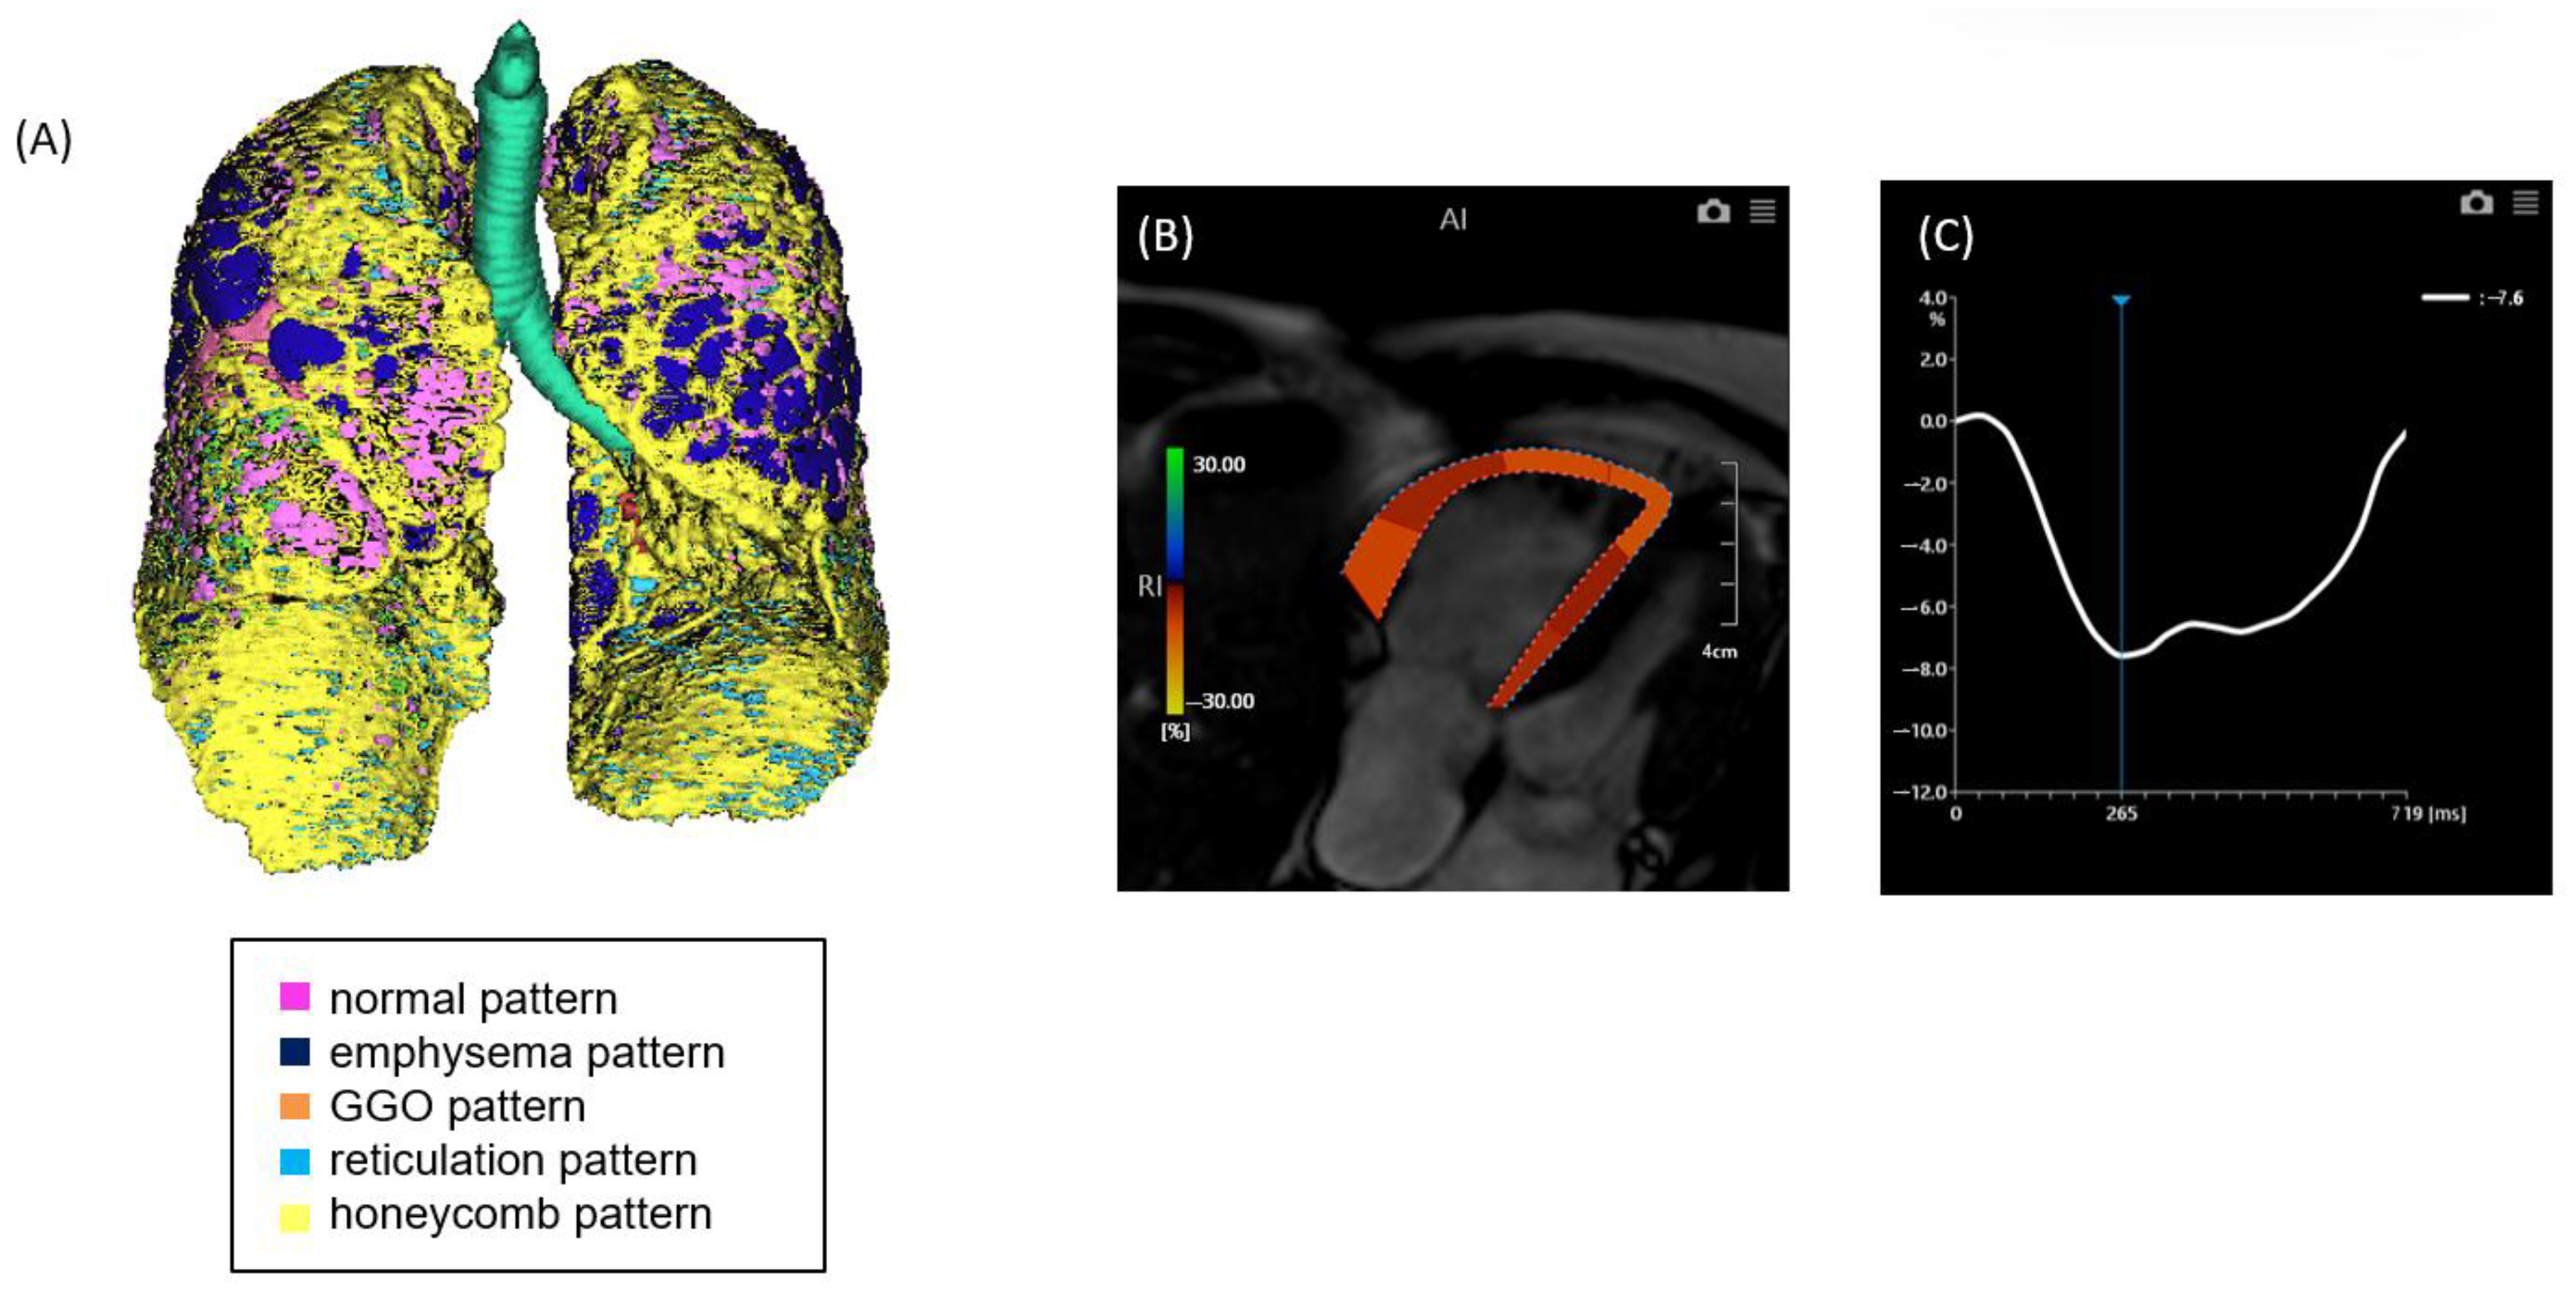

2.2. CT Image Acquisition and Analysis

2.3. MRI Image Acquisition and Analysis